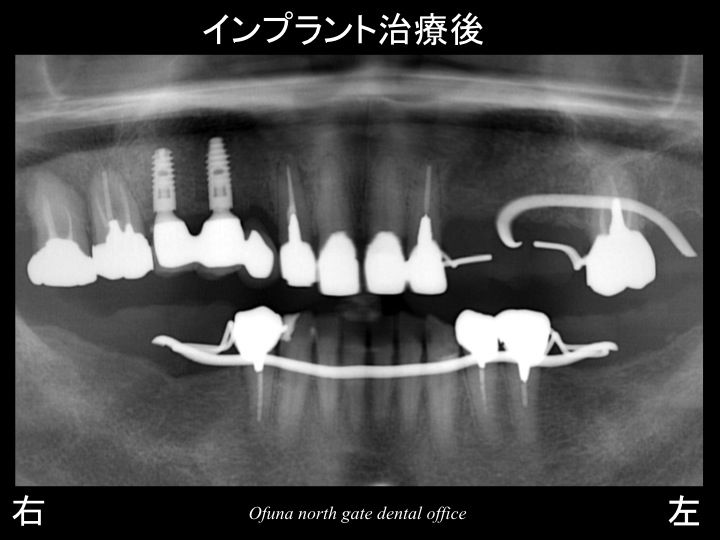

そのため、今回のインプラント治療計画では、

骨吸収の大きい部位にはインプラントを埋入しない方法を行うことにしました。

カンチレバー という治療方法です。

奥の2歯欠損部に2本のインプラントを埋入し、

手前の抜歯した部位にはインプラントを埋入せず、

被せ物を3歯分作製する方法です。

この部位のインプラント計画はこれでOKです。

そのため、今回の治療計画では、抜歯した上顎右側の3歯欠損のみ インプラント治療を行い、

他の部位は義歯(入れ歯)で対応することにしました。

使用したインプラントは、アンキロス インプラント です。